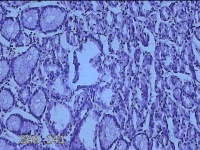

胃体粘膜

性别

女

年龄

34岁

临床诊断

胃炎;胃息肉

一般病史

胃体可见息肉样隆起。

标本名称

大体所见

灰白粉红色组织小米大一团。